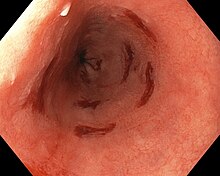

![]() | |

| Endoscopic image of Barrett's esophagus, which is the area of dark reddish-brown mucosa at the base of the esophagus. | |